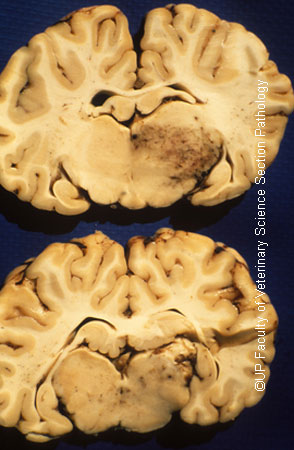

Turning sickness : infarcts in thalamus and cerebrum

| dc.description.abstract | Turning sickness or cerebral theileriosis is an uncommon aberrant form of infection by Theileria parva or Theileria taurotragi in which lymphoblasts parasitized by schizonts accumulate in cerebral vessels leading to thrombosis and infarction. In the more acute form areas of intense congestion and haemorrhage are present in the meninges and brain which are associated with ares of softening (Infarction) and discoloration of brain tissue. Thrombosed meningeal vessels are often very promiment. There may be severe haemorrhage into the ventricles. | en |

| dc.title | Turning sickness : infarcts in thalamus and cerebrum | en |